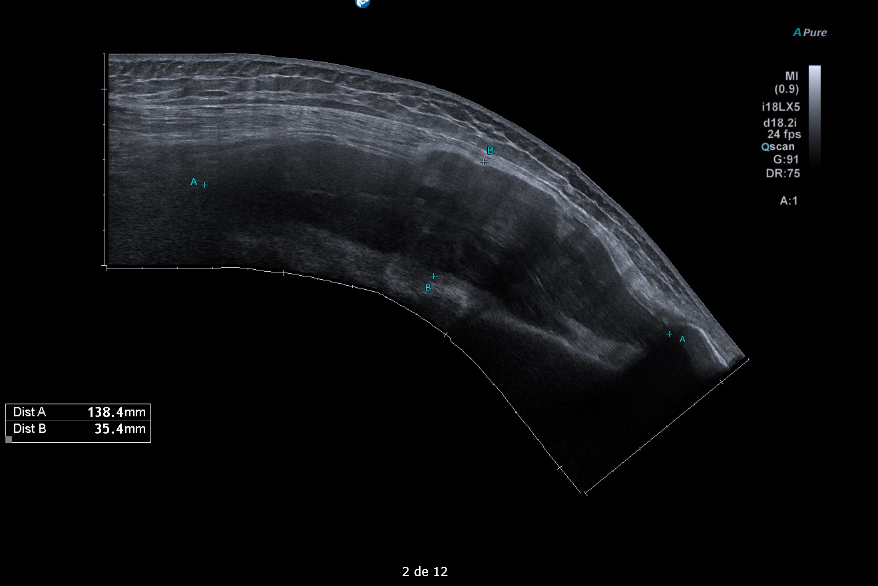

Masa sólida de partes blandas de 5 x 9 x 14 cm en compartimento femoral anterior, en profundidad al recto femoral y vastos medial y lateral. Engloba desde el tercio medio de la diáfisis hasta la rótula. Presenta polos sólidos vascularizados y zonas quísticas/necróticas.